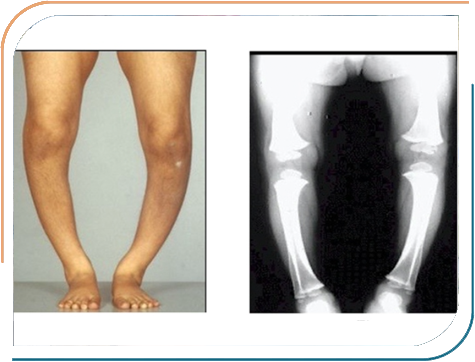

Dr. Jhala's expertise encompasses a wide range of paediatric endocrine disorders, including Growth abnormalities, Childhood Diabetes, Thyroid disorders in Children, Puberty-related concerns, Bone diseases and many other hormonal conditions in Children. She is dedicated to diagnosing and treating conditions such as Type 1 diabetes, Growth hormone deficiencies, and early or delayed puberty, all aimed at helping children lead healthier, more fulfilling lives. Her approach combines thorough clinical evaluation with the latest medical advancements, ensuring comprehensive care tailored to each child's needs.